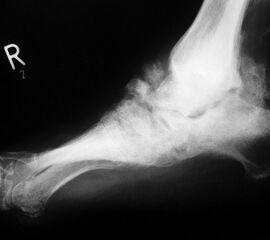

Abbildung 3

DNOAP Typ II (Abb. 3)

Typ II der DNOAP betrifft die Tarsometatarsalgelenke. Hierbei kommt es zur Ausbildung eines hochgradigen Plattfußes durch Luxation der Ossa cuneiformia und/oder naviculare. Typische Folge ist eine ausgeprägte Vorfußabduktion. Durch die hohe Druckbelastung im cuneiforme-naviculare Bezirk sind plantare Ulcerationen häufige Folge.